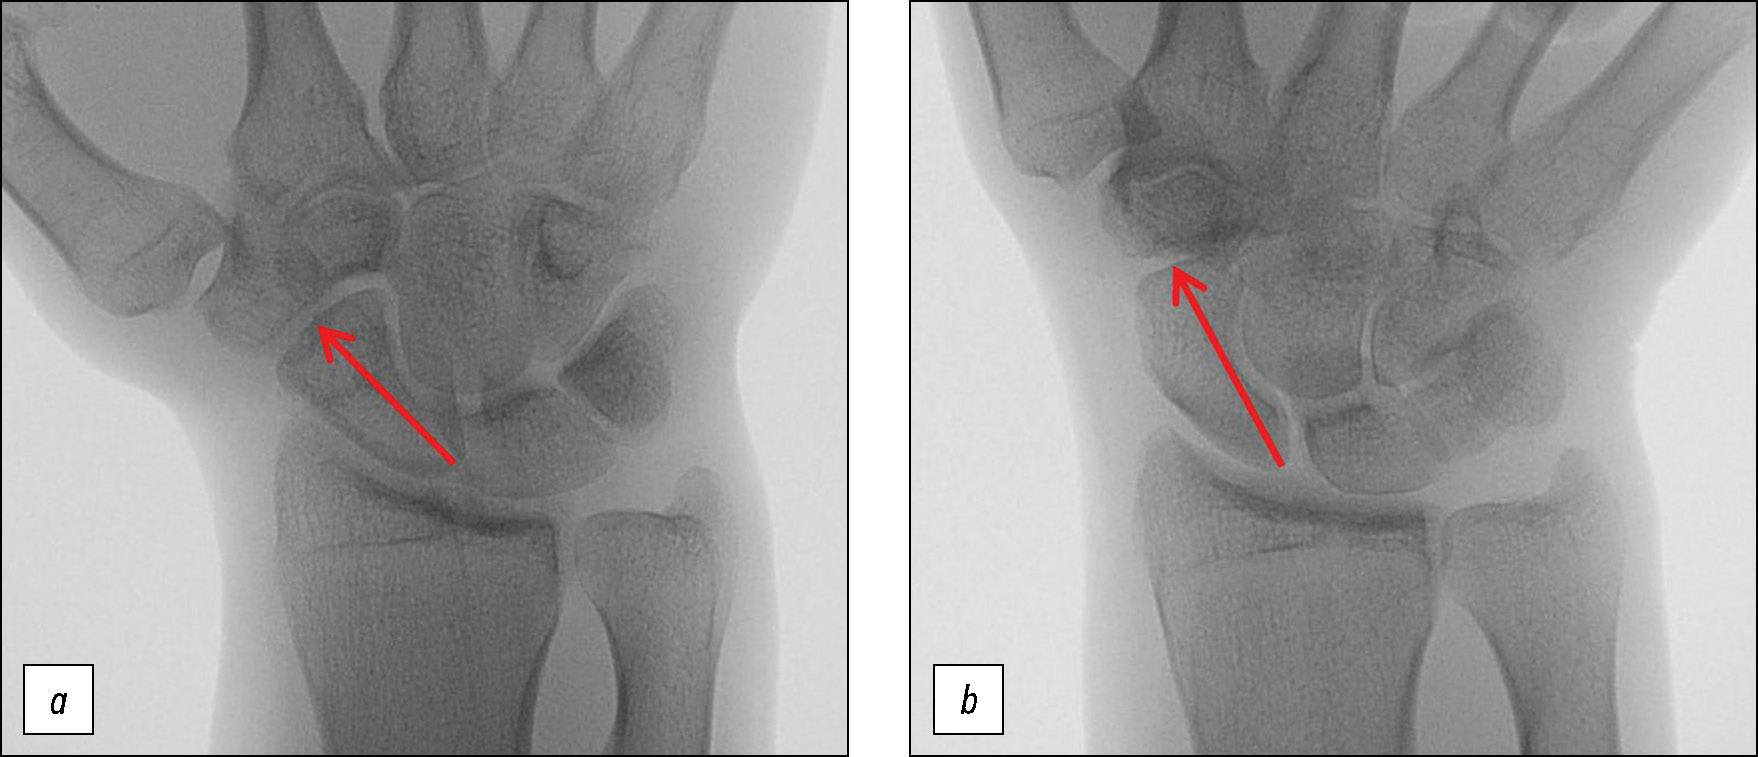

Полученные изображения переносились на персональный компьютер. При анализе рентгенограмм определяли длину ладьевидной кости. Для этого проводили продольную ось от середины проксимального полюса ладьевидной кости до середины дистальной части ладьевидной кости. Измеряли расстояние от крайних точек на этой линии (рис. 5) [7, 8].

Рис. 5. Рентгенограмма волонтёра № 3: а — рутинная укладка (R), длина ладьевидной кости 22 мм; b — укладка по Stecher, модифицированный вариант (SM), длина ладьевидной кости 28 мм. Определение продольной оси ладьевидной кости. Красная линия соединяет середину проксимального полюса ладьевидной кости и середину дистальной части ладьевидной кости. Измеряется расстояние от крайних точек на этой линии.

Fig. 5. Radiograph of volunteer #3: а — routine position (R), length of the scaphoid bone 22 mm; b — Stecher position, modified version (SM), the length of the scaphoid bone 28 mm. Determination of the longitudinal axis of the scaphoid bone. The red line connects the middle of the proximal pole of the scaphoid bone and the middle of the distal part of the scaphoid bone. The distance from these points on this line is measured.